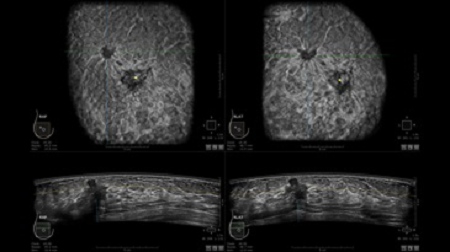

• Получение объемных 3D изображений с возможностью покадрового просмотра

• Настраиваемые рабочие протоколы

• Алгоритмы обработки изображений: алгоритм однородности изображения ткани (TEA), подавление зернистости, компенсация акустической тени от соска (NSC), определение границ молочной железы (BBD), определение стенки грудной клетки

• Отображение объемных 3D ультразвуковых изображений, которые состоят из традиционных поперечных и воссозданных коронарных и сагиттальных проекций

• Стандартизованная ориентация изображения: «толстый срез» в коронарной плоскости; поперечная; сагиттальная плоскость; радиальный и антирадиальный поворот изображения; просмотр исключительно области интереса

• 360 ° APC - отображение области по «любой точке компаса»

• Одновременный просмотр двух изображений для сопоставления в коронарной плоскости